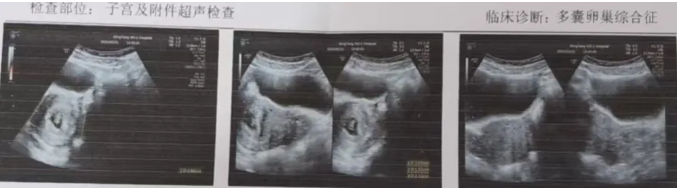

李桂香医生接诊后,详细了解王女士的病史,以及行必要检查,发现她患有多囊卵巢综合征,排卵障碍,再加上她精神高度紧张,甚至焦虑,所以迟迟没能怀孕成功。

李桂香医生了解病因后,给予王女士心理疏导,让其缓解焦虑的同时,改善身体代谢状况,于今年1月份给予促排卵治疗,谨慎用药,促排成功。